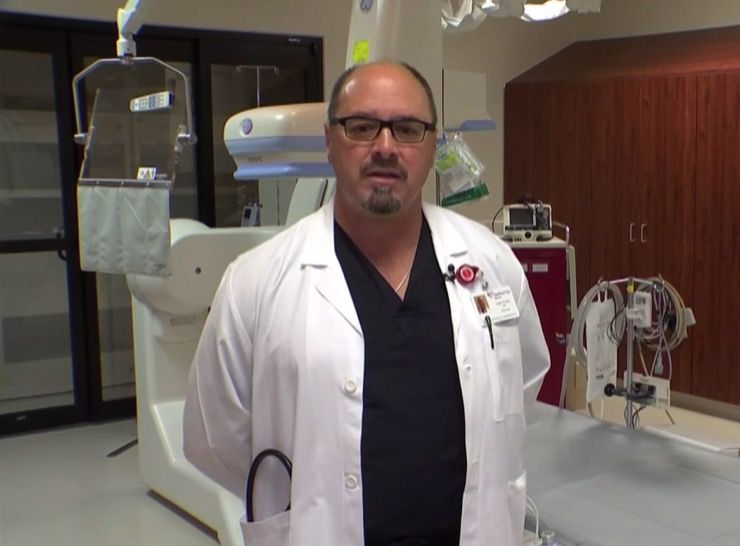

Worrying Condition

Cardiologist Dr. Gary Fazio was on call when Ed Burkett was brought in. He recalled that by the time Burkett actually arrived in the emergency room, he looked awful. Over the next harrowing hour, this particular patient would prove to even a veteran physician like Fazio what the human body is capable of.

A Near Thing

It was a near thing to the end and one that Dr. Fazio considers nothing short of miraculous. “There are miracles that happen every day here,” he explained while talking to NBCDFW. The astonished doctor added that “Sometimes it takes someone like Ed to make it so obvious.” The incident wasn’t just miraculous, it was also unheard of.

44 Attacks, 20 Years

Dr. Fazio had been in medicine for more than 20 years and in two decades of working with patients and specifically the heart, he had never seen someone survive after 44 separate attacks. He had never come close to witnessing that kind of physical and emotional fortitude. “Generally speaking, after that many defibrillations, you’ve lost that battle,” he explained.

Great For Everyone

Dr. Fazio said that Burkett’s amazing story has lifted the spirits of staff and patients alike in his hospital. His story of survival is a reminder that where there is life, there’s hope. He adds that “if you have faith, anything is possible.” But Burkett is hardly the first cardiac patient to defy the odds in recent years.